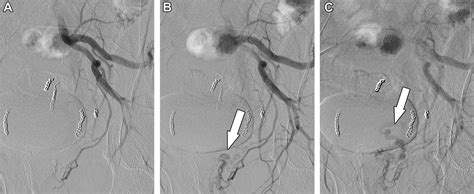

Hemorrhoid Artery Embolization is a cutting-edge, image-guided procedure performed by interventional radiologists. Unlike traditional surgery, which physically removes the hemorrhoidal tissue, HAE works by targeting the blood supply that feeds the hemorrhoids. By reducing the arterial blood flow to the hemorrhoidal plexus, the procedure causes the hemorrhoids to shrink over time, effectively alleviating symptoms like bleeding, pain, and protrusion.

Because it is a minimally invasive technique, it does not require general anesthesia or incisions in the sensitive anal region. Instead, a tiny catheter is guided through a blood vessel in the wrist or groin to the specific arteries supplying the hemorrhoids. Small particles are then injected to block these vessels, successfully reducing the pressure and engorgement of the hemorrhoidal tissues.

2. Guidance: Using real-time X-ray imaging (fluoroscopy), the radiologist navigates a microcatheter through the vascular system.

3. Embolization: Once the specific hemorrhoidal arteries are identified, specialized embolic agents are injected to reduce the blood supply.

Clinical studies have consistently demonstrated that Hemorrhoid Artery Embolization is highly effective in controlling symptoms, particularly rectal bleeding. Most patients notice a significant improvement within a few weeks as the hemorrhoidal tissue gradually shrinks. Because the blood supply is permanently reduced, the recurrence rate is low, provided that patients maintain a lifestyle that prevents chronic constipation and straining.